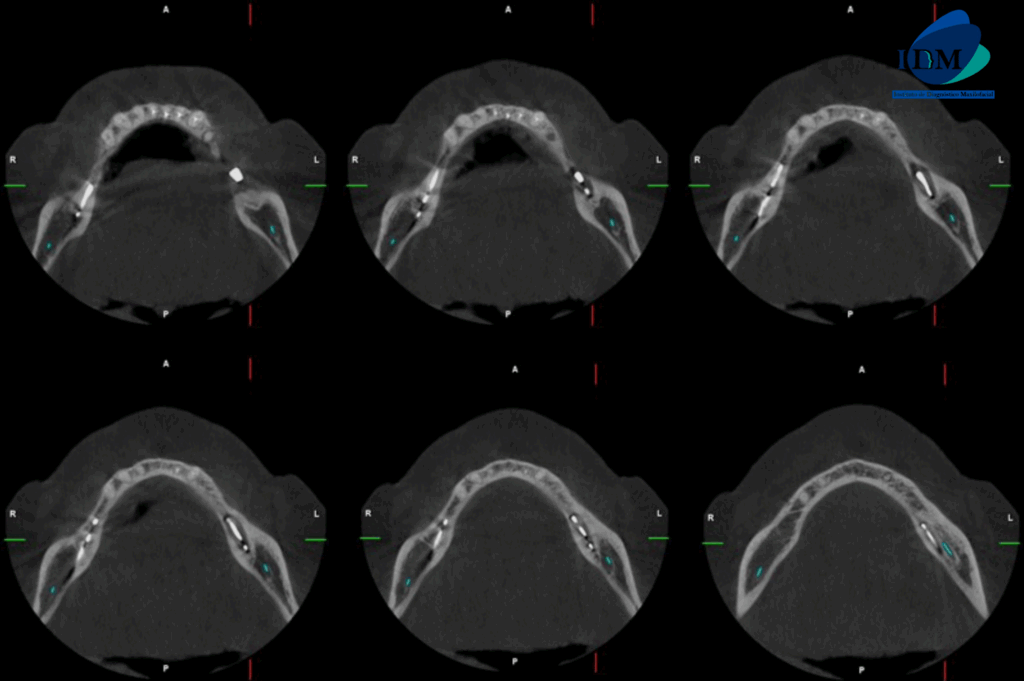

Al observar la tomografía computarizada de campo mediano se puede observar que los implantes en el maxilar inferior son efectivamente de tipo laminares o de lámina perforada, además se puede observar en vistas axiales la presencia de una imagen hipodensa circundante al implante de zona de pieza 36 (flecha azul), en vistas transaxiales y tangenciales se evidencian pérdida de continuidad de tejido óseo en tercio cervical; características que no presenta el implante en zona de pieza 46 (flecha amarilla- vista axial). Signos imagenológicos compatible con perimplantitis.

CORTES AXIALES